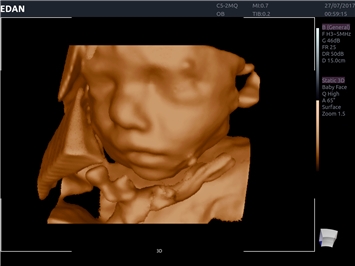

• 3D/4D-визуализация с автоматическим редактированием объема (eFace)

• Автоматизированные измерения в акушерстве

• Акушерства и гинекологии